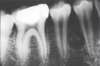

What is this radiographical finding?

Metastatic Carcinoma to Jaw Bones

C. Periapical image of a metastatic lesion of breast carcinoma; note the irregular widening of the periodontal membrane spaces and patchy sclerotic bone reaction, especially around the roots of the molars